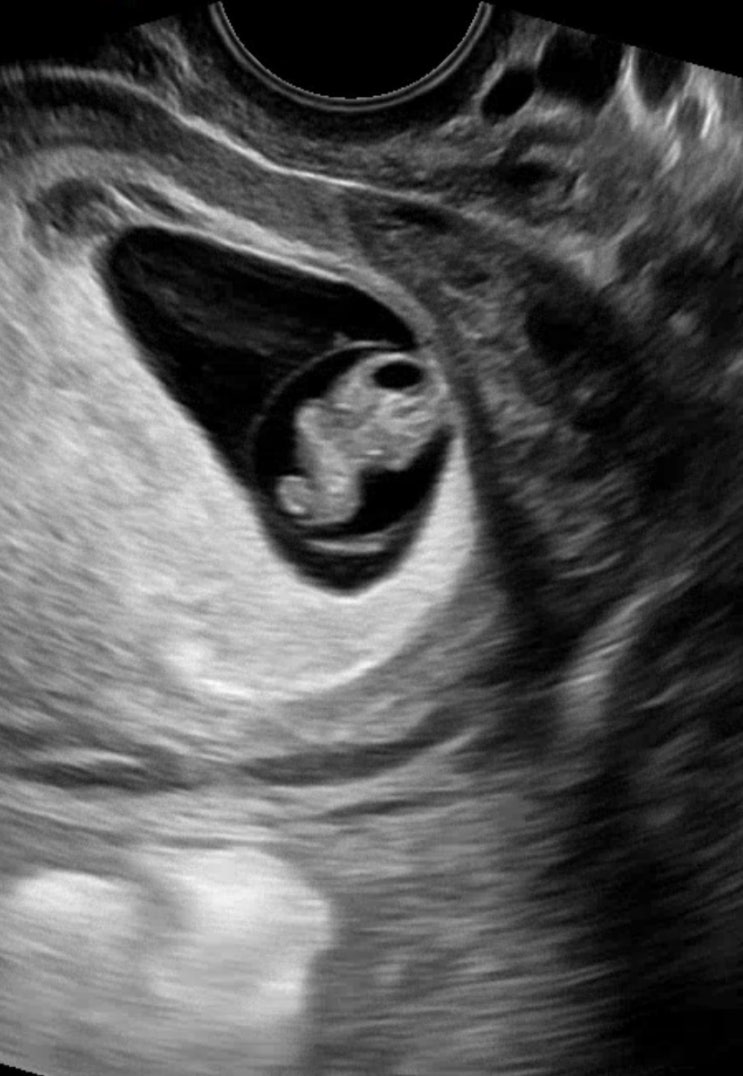

다솜이 첫만남

9/16일 첫만남 한번의 유산 다시 만난 소중한 아가 아프지말고 건강하게만 태어나다오 “애틋하게 사랑하는...

다솜이

11/19